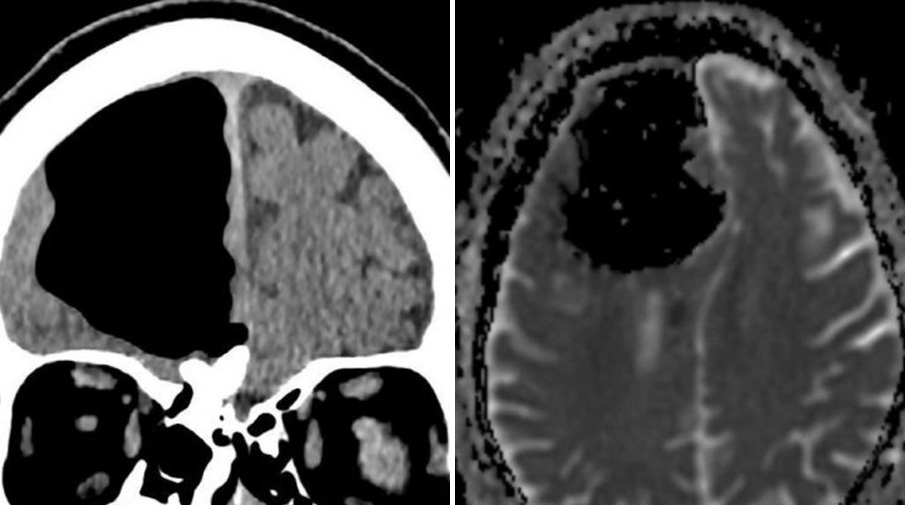

Пустоту вместо правой лобной доли мозга обнаружили врачи у пожилого мужчины, жаловавшегося на проблемы с координацией. Как оказалось, сама лобная доля никуда не делась — в черепе образовалось пневматоцеле, заполненная воздухом полость.

Исходя из симптомов, врачи предположили, что пациент пережил инсульт, и провели компьютерную томографию мозга.

Однако результаты их озадачили. Там, где должна была находиться правая лобная доля, была пустота.

Результаты МРТ, впрочем, показали, что сама лобная доля никуда не делась. Но в передней части черепа образовалась заполненная воздухом полость, достигавшая 9 см в поперечнике — пневматоцеле. Обычно пневматоцеле наблюдается после травм лица, респираторных инфекций или хирургических операций в области черепа, но ни с чем подобным пациент не сталкивался.

Также на МРТ врачам удалось выявить остеому, доброкачественную опухоль кости, локализованную в области решетчатой кости, которая отделяет носовую полость от полости черепа. Повреждение кости и позволило воздуху попадать в череп, работая как односторонний клапан.